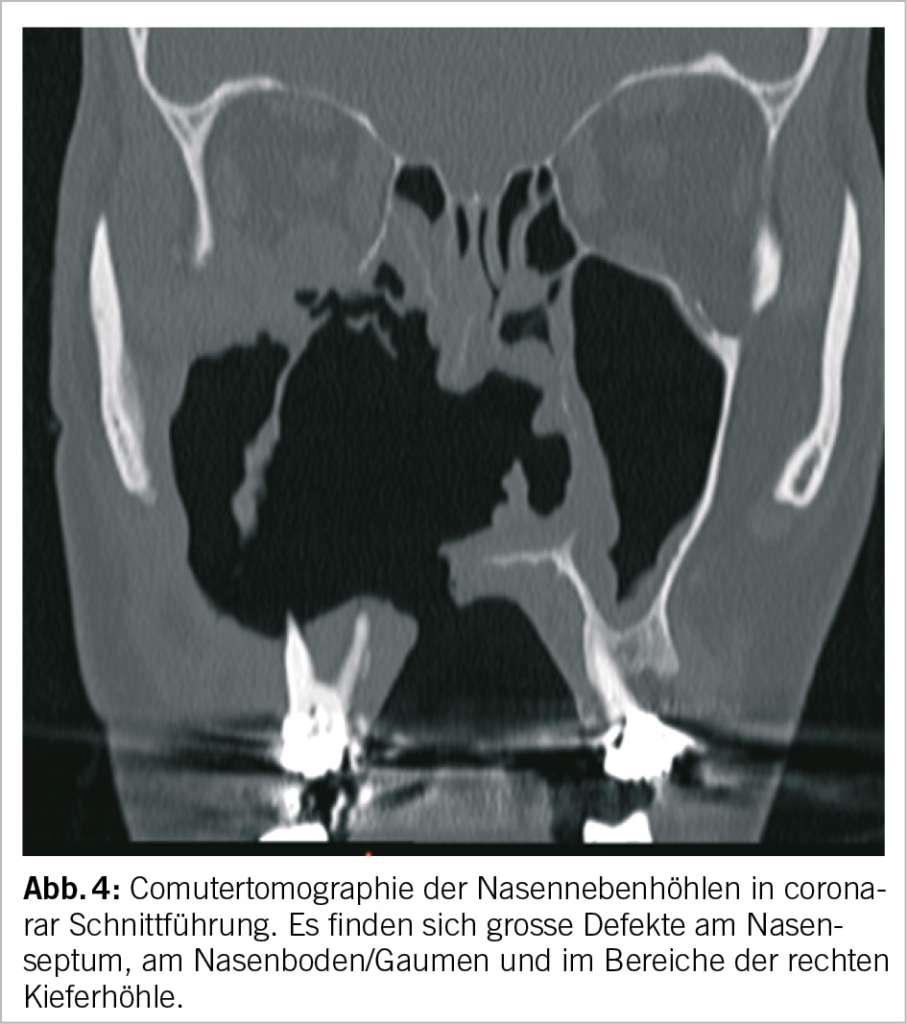

C. Computertomographie der Nase und Nasennebenhöhlen

Antwort: Richtig sind alle Antworten. Aus der er­gänzenden Anamnese erfahren Sie bei genauerem Nachfragen, dass der Patient regelmässig Kokain konsumiert. Bei der Vermutung einer Granulomatose lassen Sie in den Laboruntersuchungen unter anderem die ANCAs bestimmen. Da die Verhältnisse in der Nase sehr unübersichtlich sind und grosse Destruktionen vorliegen, veranlassen Sie eine Bildgebung, wobei neben der Computertomographie auch ein MRI möglich wäre. Zur Entnahme von endoskopisch kontrollierten, gezielten Schleimhautbiopsien in Oberflächenanästhesie überweisen Sie den Patienten an eine ORL-Fachärztin, mit welcher Sie regelmässig zusammenarbeiten. Zehn Tage später kommt der Patient wie geplant zu Ihnen in die Sprechstunde, um die Resultate zu besprechen. Sie erklären ihm den Radiologiebefund und informieren ihn über die Laborresultate. Hier fallen die positiven c-ANCA auf. Die Histologie zeigt eine chronische Entzündung mit Granulomen.

Bei unserem Patienten mit regelmässigem Kokainabusus liegt eine toxische Ursache dieser grossflächigen Destruktionen in der Nase, der Kieferhöhle und des Gaumens vor. Wie aktuelle Abwasseruntersuchungen zeigen, ist der Konsum von Kokain in der Schweiz weit verbreitet und muss bei Läsionen in der Nase gezielt erfragt werden. Kokain führt einerseits selbst zu einer ANCA-assoziierten Vaskulitis, welche oft schwierig von einer Granulomatose mit Polyangiitis zu differenzieren ist. Beide weisen im Labor nämlich positive c-ANCA auf. Hier kann neben der Anamnese die Bestimmung der Anti-Elastase-Antikörper weiterhelfen. Andererseits ist Kokain häufig mit Levimasol gestreckt. Levamisol ist ein Antihelminthikum, welches in der Veterinärmedizin eingesetzt wird. Zudem hat es eine immunmodulierende Wirkung und soll auch leicht euphorisierend wirken. Als Nebenwirkung kann es zu Haut- und Schleimhautnekrosen führen. So zeigt auch unser Patient neben den eindrücklichen Befunden in der Nase eine Hautnekrose am Rücken.